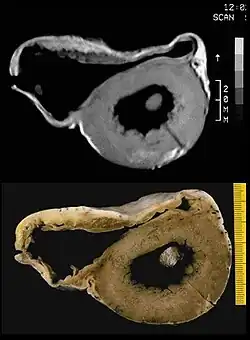

In der ursprünglichen rein "rechtsventrikulären" Form wurde beschrieben, dass mit dem Fortschreiten der Erkrankung immer mehr Muskulatur der rechten Herzkammer durch Fettgewebe ersetzt wird, wodurch sich die rechte Herzkammer vergrößert. Selten finden sich Einschränkungen in der Pumpfunktion des Herzens. Häufiger ist der bei körperlicher Belastung, wie beispielsweise Leistungssport, ausgelöste plötzliche Herztod (PHT) oder „Beinahe“-PHT, insbesondere bei jungen Menschen. Die Diagnose kann mittels Echokardiografie, MRT, EKG und McKenna-Score gestellt werden. Zur Behandlung kann ein Kardioverter-Defibrillator implantiert werden. Sportliche Belastungen sollten vermieden werden. Eine Herztransplantation ist in vielen fortgeschrittenen Fällen die Ultima Ratio.

Angeborene, seltene Herzmuskelerkrankung mit schwammartig aufgetriebener Muskulatur vor allem in der Spitze der linken Herzkammer, die tiefe Aushöhlungen (Sinusoide) zwischen Muskelfasern (Trabekeln) aufweist, die mit der Herzhöhle verbunden sind. Bei der Isolierten Nonkompaktion des Herzmuskels (Syn: Non-Compaction-Kardiomyopathie, linksventrikuläre Hypertrabekulation, spongy myocardium) hat sich der Herzmuskel aus seinem losen Maschennetz während der frühen Embryonalphase nicht weiter verdichtet (schwammiges Myokard). Gehäuft bei Skelettmuskelerkrankungen, auch in Kombination mit komplexen zyanotischen Herzfehlern.

Die Diagnose wird durch Echokardiografie, MRT oder Angiografie der linken Herzkammer bei einer Herzkatheteruntersuchung gestellt. Unklar ist der klinische Verlauf. Fälle von schwerem Herzversagen, Thromboembolie, Arrhythmien und plötzlichem Herztod sind bekannt. Familiär gehäufte Fälle wurden beschrieben, wobei Mutationen der Z-Scheibe, der Mitochondrien und des G4.5-Gens für Tafazzin isoliert werden konnten.[8]